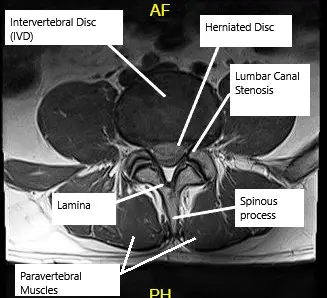

MRI showing Lumbar Canal Stenosis

The lumbar spine consists of five vertebrae connected by intervertebral discs and facet joints. These structures allow flexibility while protecting the spinal cord and nerves. The spinal canal houses the nerves that branch out to the legs. When the canal narrows, nerves become compressed, causing symptoms of pain, numbness, or weakness in the lower body.

- MRI: Reveals soft tissue and nerve compression.